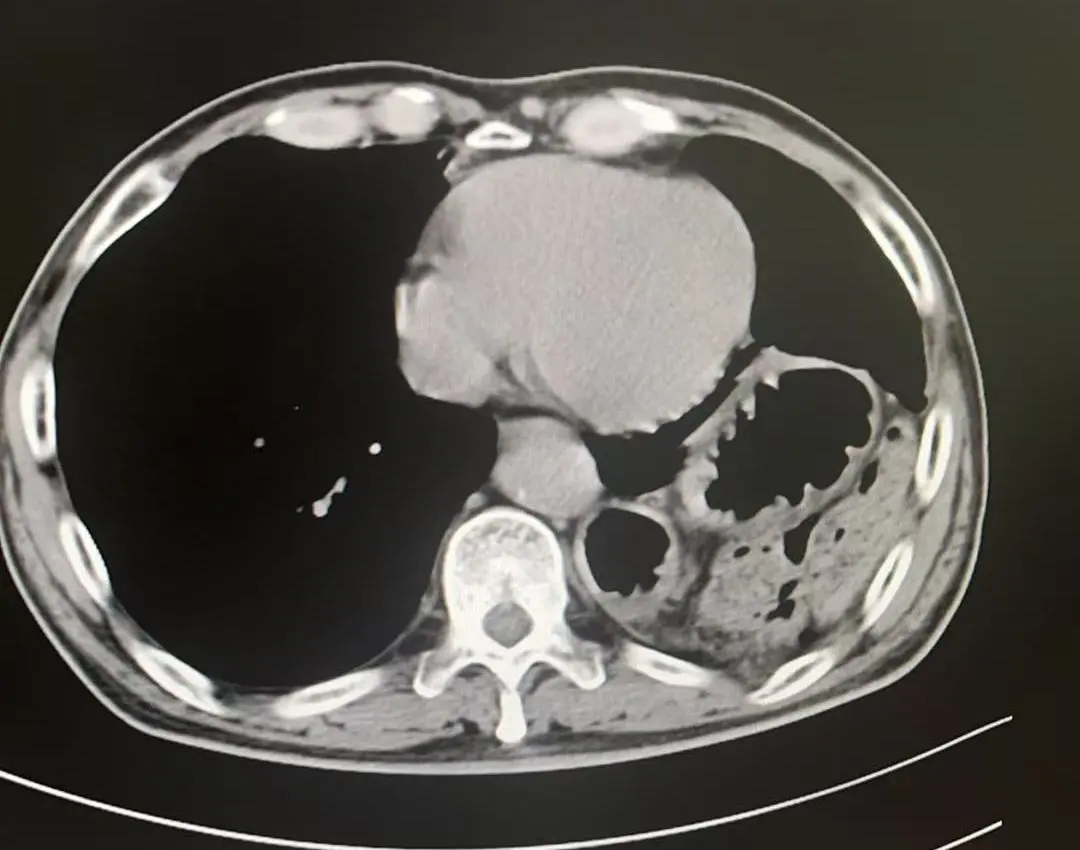

术中发现胃、结肠、小肠及脾脏疝入胸腔且与周围组织严重粘连,部分脏器难以通过微创完全复位。孙振教授果断决策,通过10厘米切口精细分离粘连,成功还纳全部脏器并牢固修补缺损,杜绝复发隐患。

术后影像

膈疝修补如拆“定时炸弹”,需松解粘连、归位脏器、修复缺损三步精准到位。团队采用阶梯策略,在确保手术效果的同时最大程度降低风险、减少创伤。术后,刘大爷的症状迅速缓解,现已康复出院,重归正常生活。